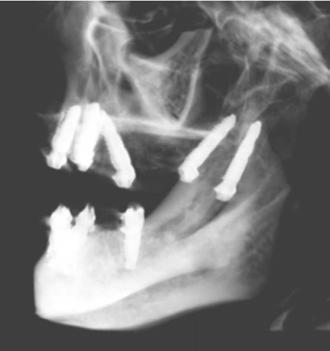

An 80-year-old male with a relatively clean medical history was referred for full-arch immediately loaded maxillary implant treatment. The patient had been previously treated with maxillary dental implants in a traditional All-on-X approach. The referring clinician noted that the patient’s bone was extremely “soft” and that insertion torque for most of the implants was very low. Although these implants were not immediately loaded, they ultimately failed and created large oroantral communications. While the communications were ultimately closed, extremely large

Figure 7 (left): CBCT slice (sagittal view) for vertical measurement from subnasal bone to prelacrimal bone engagement point. Figure 8 (middle): Panoramic radiograph of patient with history of failed All-on-X treatment, oroantral fistulae, and thickened Schneiderian membranes. Figure 9 (right): Intrasurgical photo of transnasal dental implant traversing the nasal cavity and engaging the base of the inferior concha

defects resulted in the floor and walls of the maxillary sinuses (Figure 8). CBCT analysis revealed a significantly thickened left Schneiderian membrane and occluded osteomeatal complex. The patient was referred to ENT for a Functional Endoscopic Sinus Surgery (FESS) procedure. Upon healing, a new CBCT was taken and evaluated for potential treatment.

Due to the atrophic nature of the maxilla, treatment following the PATZi protocol was planned.6,17,20 CBCT evaluation revealed pterygomaxillary bone appropriate for pterygoid implants allowing for posterior arch support and cantilever elimination. The zygomas were of adequate height and width to accommodate multiple zygomatic implant fixtures bilaterally. PLACATE guidelines were used to evaluate the patient for potential treatment with transnasal implants. With Simmen 3 nasolacrimal canal classification, ≥ 3 mm of prelacrimal bone, ≥2 mm subnasal bone, and ≤ 25 mm to the Z-point, the patient satisfied all PLACATE parameters. Accordingly, a treatment plan of bilateral pterygoid, single zygomatic, and transnasal implants was agreed upon.

Following the induction of general anesthesia, extraoral and intraoral local anesthesia was applied. To avoid exposing the large subantral bony defects, mini-flaps were elevated at the pterygoid landing areas to expose the hamular notch. The pterygoid fossa was identified via probing, and pterygoid implant placement ensued. Following the PATZi protocol, bilateral pterygoid implants were placed first and both achieved insertion torque between 45+ Ncm.

Following PATZi, anterior support was sought next. As such, the nasal mucosa was elevated to expose the floor of the nasal cavity and the bone of the inferior conchae. A pair of 25 mm transnasal implants were placed, and each achieved high insertion torque of 45+ Ncm (Figures 9-11). Continuing with the PATZi protocol and treatment plan, 42.5 mm long zygomatic implants were placed in both zygomas. The zygomatic implants were placed using an extrasinus approach and both achieved insertion torque of 45+Ncm. Buccal fat pedicles were advanced bilaterally to cover extrasinus portions of the zygomatic implants, and flap closure was achieved with 4-0 chromic gut suture. The patient was immediately temporized with a screw-retained transitional bridge (Figure 12), and a final zirconia restoration was delivered after 8 months of healing (Figure 13).

Figure 10 (left): CBCT slice (coronal view) of transnasal dental implants engaging the Z-point. Figure 11 (middle): CBCT slice (sagittal view) of transnasal dental implant engaging prelacrimal bone ventral to the nasolacrimal duct. Figure 12 (right): 3-dimensional CBCT rendering of patient treated with transnasal, zygomatic, and pterygoid dental implants via the PATZi protocol

Figure 13: Panoramic radiograph of patient with final zirconia restoration